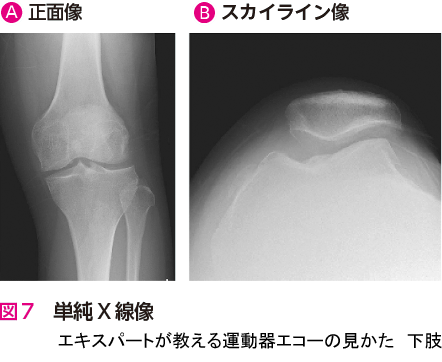

人工関節置換術を施行した症例です.エコー検査での膝関節前方(長軸像)では,膝蓋骨の骨棘と関節水腫を観察できます.また,膝関節内側(長軸像)では,内側側副靭帯浅層の直下に骨棘と内側半月板を観察できます.骨棘は大腿骨と脛骨から大きく張り出しています(図1🅑*).